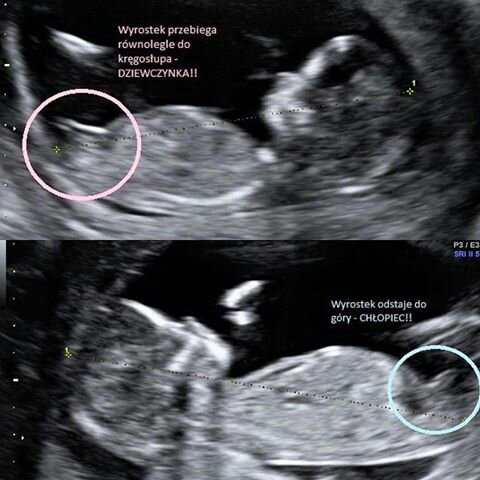

Płeć dziecka

Mojej dzidzi ten wyrostek ewidentnie leży i mam nadzieję że dziewuszką pozostanie. 2 lekarzy twierdzi że dziewuszka, a fotkę mam wyraźną

U mnie tez tak jest na fotce ze wyrostek jest na płasko. Wiec miejmy nadzieję ze tak jiz zostanie [emoji6]